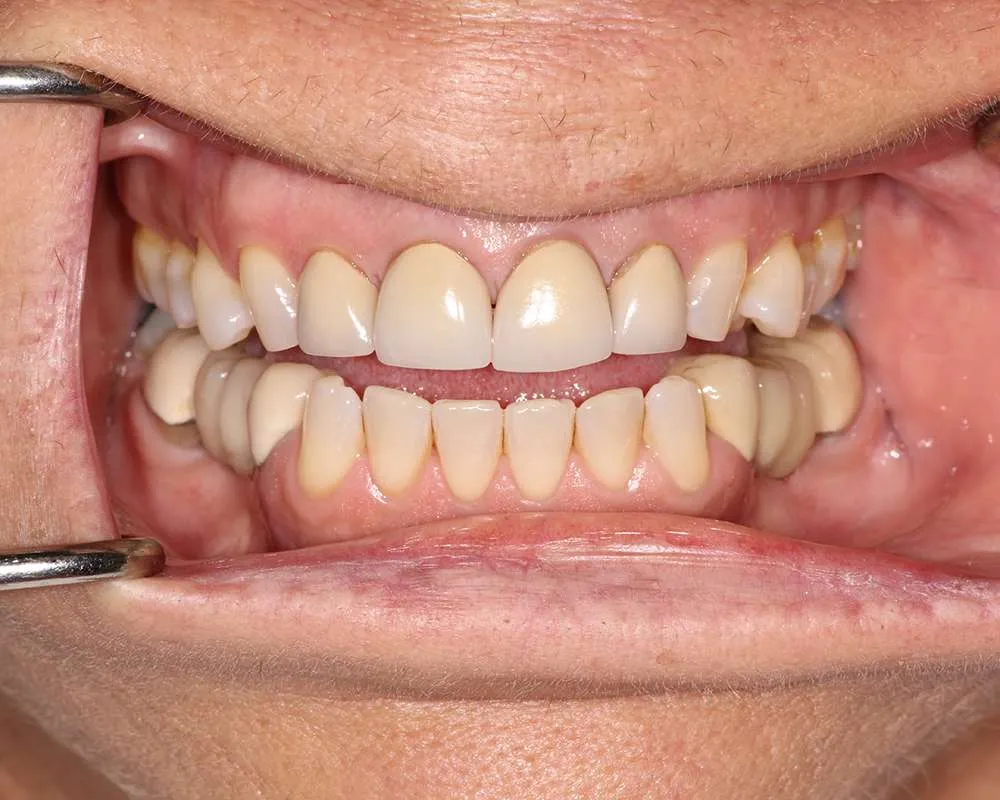

At Dr. Paul O'Malley's practice, we specialize in ultra-thin veneers that offer a minimally invasive solution for achieving a beautiful, natural-looking smile. Our approach focuses on providing aesthetic enhancements while ensuring the health and integrity of your natural teeth. These veneers are meticulously crafted from high-quality materials that closely mimic the appearance and texture of natural enamel. By utilizing advanced techniques, we ensure that the application process involves minimal alteration to your existing tooth structure. This method not only enhances the aesthetic appeal of your smile but also maintains the strength and health of your teeth, providing you with a durable and long-lasting solution.

Ultra-thin veneers are a type of cosmetic dental restoration made from high-quality, durable materials that expertly mimic the translucency and texture of natural enamel. These advanced veneers offer a revolutionary solution compared to traditional veneers, which often necessitate significant removal of tooth enamel. Designed to be as thin as a contact lens, ultra-thin veneers require minimal tooth alteration, thereby preserving more of your natural tooth structure. This innovative approach not only maintains the health and integrity of your teeth but also ensures a stronger and longer-lasting result. By choosing ultra-thin veneers, you benefit from a minimally invasive treatment that enhances your smile while supporting your overall oral health.

Ultra-thin veneers are crafted from high-quality materials that closely resemble the look and feel of natural teeth. The translucency and texture of these veneers mimic the appearance of real enamel, ensuring that your smile looks natural and aesthetically pleasing. Each veneer is custom-made to match the color, shape, and size of your existing teeth, blending seamlessly with your natural smile. This attention to detail ensures that your veneers are virtually indistinguishable from your natural teeth, providing you with a flawless, beautiful smile.